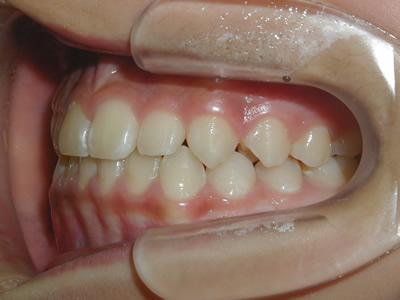

上顎の劣成長 (成長不足) による反対咬合で、上顎は拡大装置と上顎前方牽引装置を併用し前方方向への成長を促して前歯の咬み合わせを改善した後に、上下顎の前歯をマルチブラケット装置で並べました。治療の期間は2年でした。

1期治療終了時